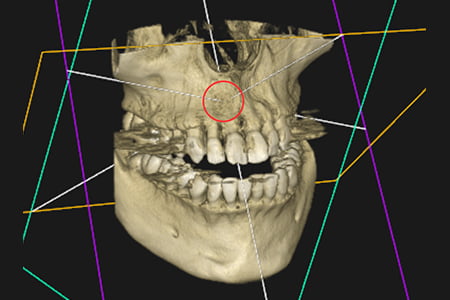

治療例3

| 症状 | 左上の前歯が急に疼く様になった |

|---|---|

| 治療方針 | 大きな骨欠損を認められる為、精密根管治療を行い骨欠損部位が改善するか経過を追う |

| 治療期間 | 10ヵ月 |

| 治療費用(税込) | ¥468,600 ※2歯分 |